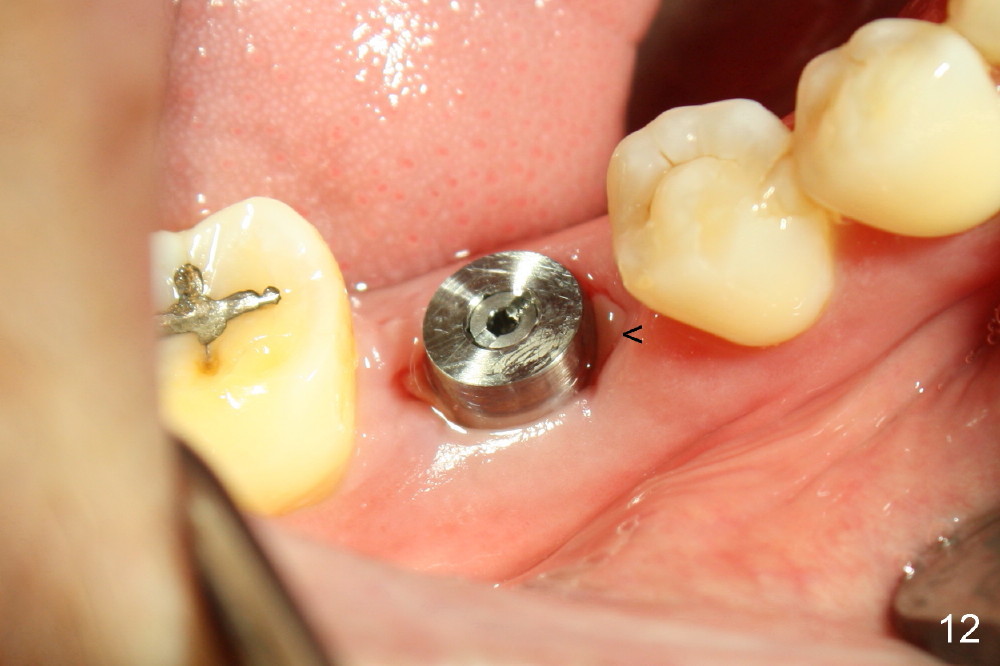

Fig.12 is taken 1 week post implantation with formation of fresh granulation tissue mesially (<).